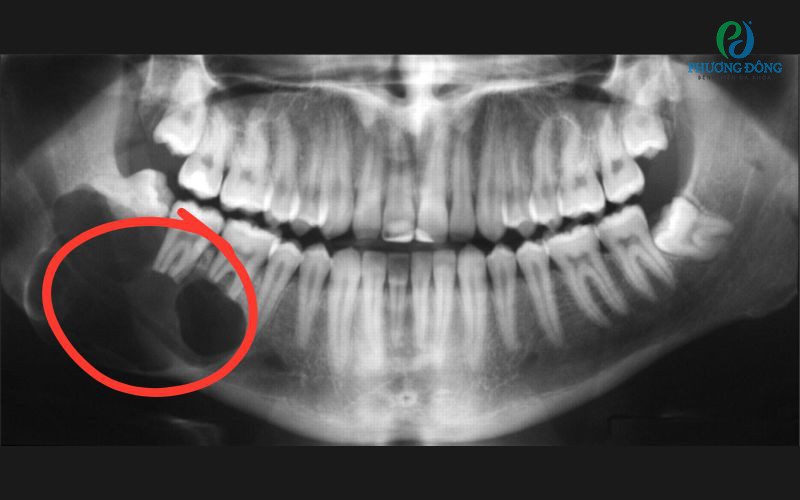

Đặc biệt, các chuyên gia y tế cho hay: Người bị ngắn lưỡi còn có thể gặp các vấn đề về cấu trúc hàm mặt, bao gồm hàm dưới kém phát triển, khớp cắn không đều, và răng mọc lệch. Bên cạnh đó, họ cũng gặp nhiều khó khăn khi chăm sóc răng miệng và có xu hướng dễ mắc các bệnh sâu răng và viêm nướu hơn.